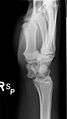

The lunate bone is the most frequently dislocated carpal bone.

Dislocated lunate

Dislocated lunate- Wrist joint. Deep dissection. Posterior view.

- Wrist joint. Deep dissection. Posterior view.